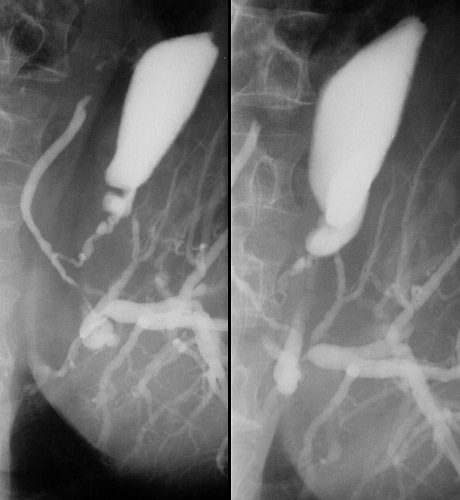

| By cholangiography there is dilation of the biliary tree above the cystic duct as a consequence of the presence of a mass lesion involving the common bile duct. This proved to be an adenocarcinoma. Such a rare primary extrahepatic biliary tract neoplasm is known as a "Klatskin tumor". |